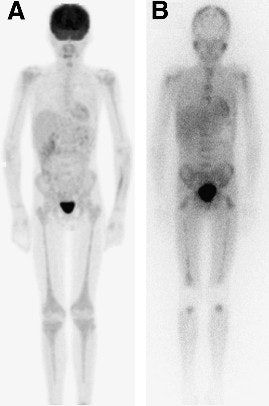

| Image of a 13-year-old male with stage IV neuroblastoma after initial chemotherapy shows FDG-PET (A) demonstrating mild diffuse bone marrow uptake extending throughout axial and appendicular skeleton in response to marrow expansion. I-123 MIBG (B) illustrates uptake in diffuse bone or marrow metastases. Researchers noted the absence of I-123 MIBG uptake in mid- or distal humerus and mid- or distal tibia. Images courtesy of the Journal of Nuclear Medicine, Cincinnati Children's Hospital Medical Center, and St. Jude Children's Research Hospital. |